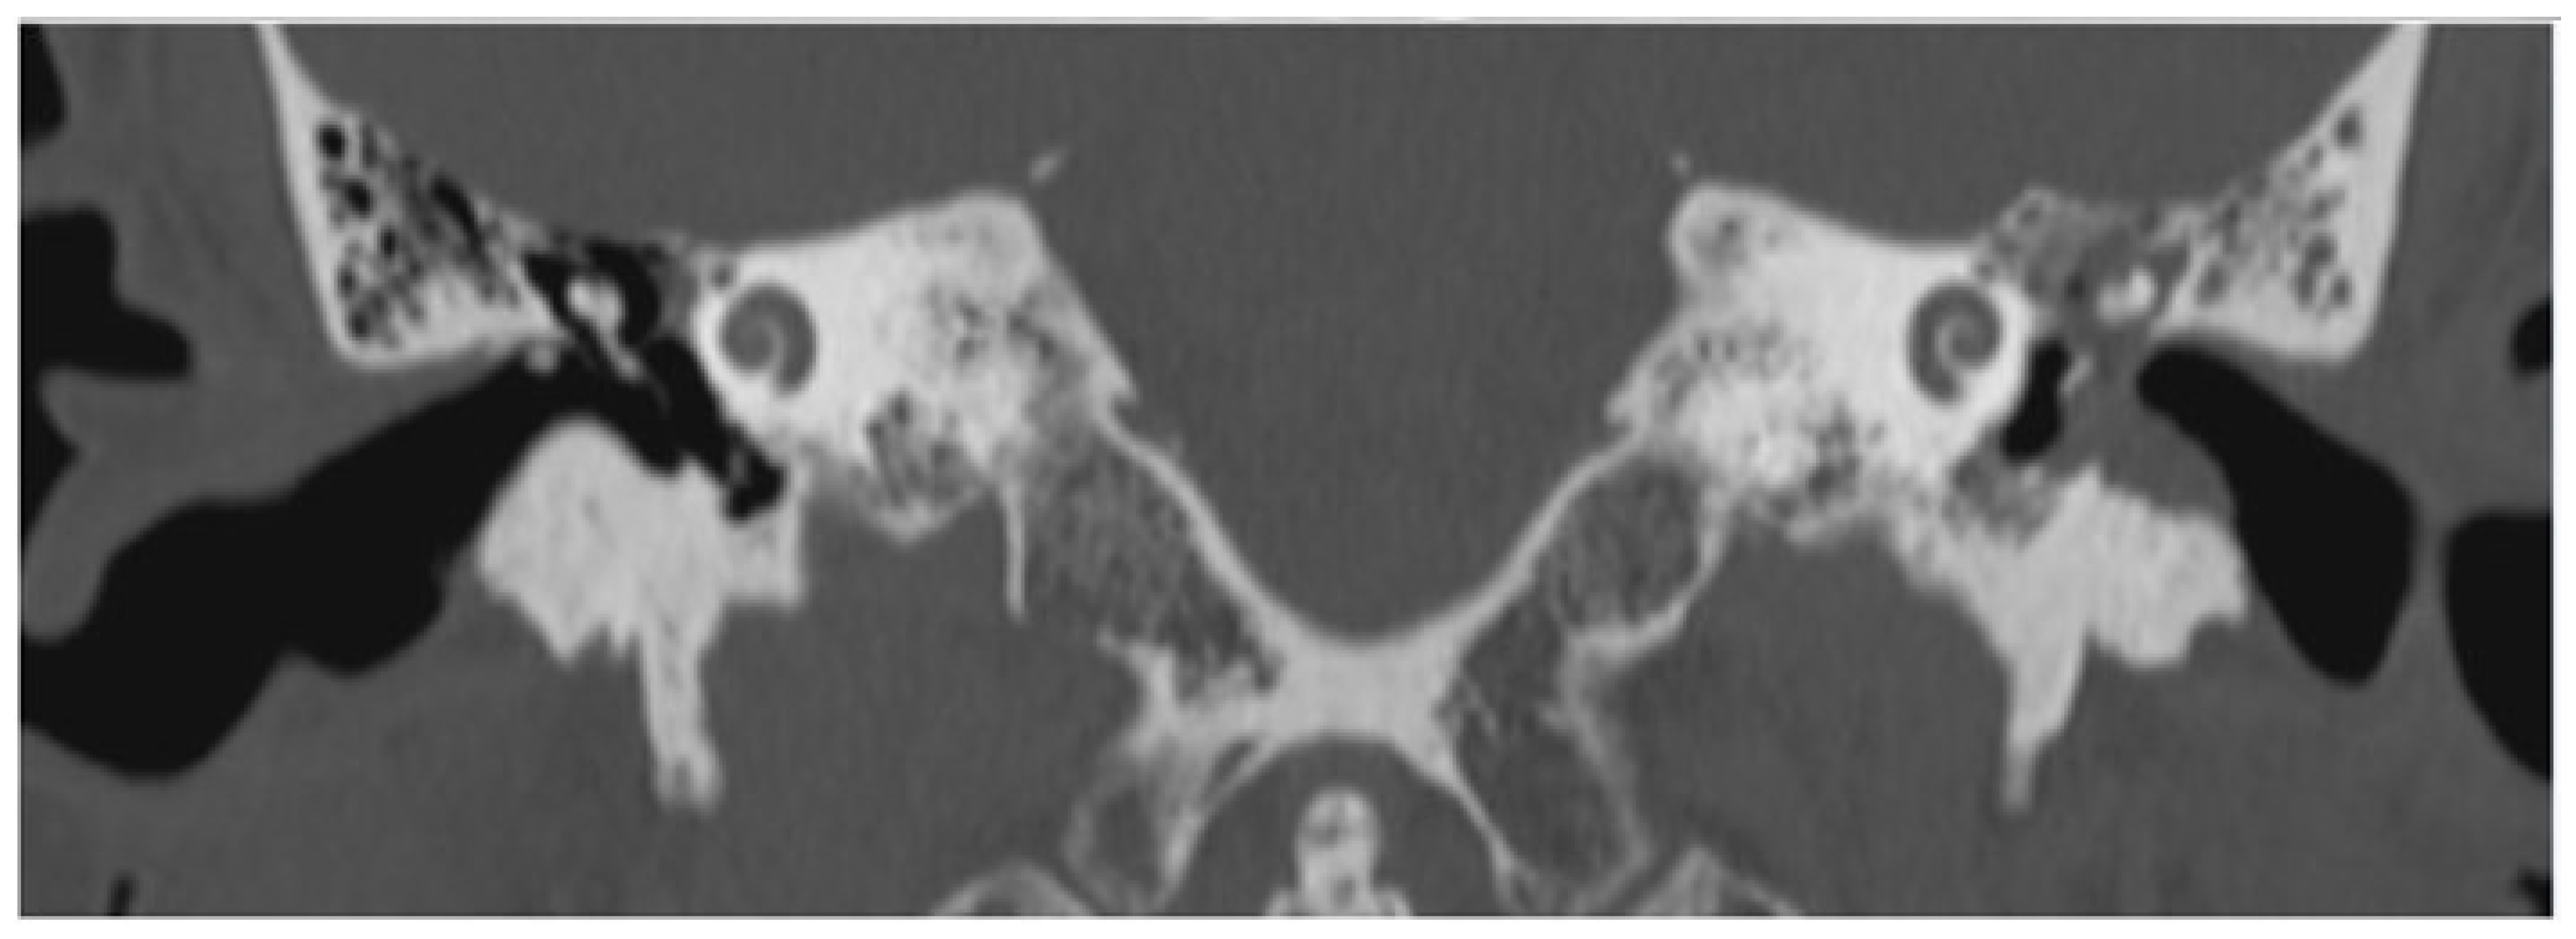

3.1. Patient 1

3.2. Patient 2

3.3. Patient 3